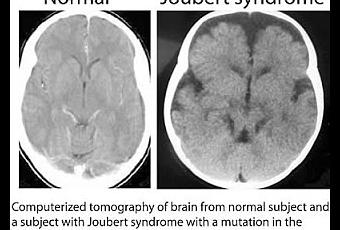

Tomographie à émission de positrons du cerveau d'un sujet normal (à gauche) versus un sujet atteint du Syndrome de Joubert (à droite).

Source iconographique: http://ucsdnews.ucsd.edu/newsrel/health/10_20_Gleeson.asp